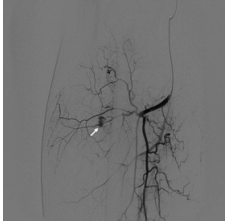

74 56 歲男性,無外傷病史,主訴三天前,右大腿持續腫脹、 疼痛而急診就醫,CT 和 circumflex femoral arteriography 如 圖示,最適切處置方式為:

(A)經導管動脈栓塞術(Transcatheter arterial embolization) (B)緊急開刀止血 (C)行保守療法輸血 (D)施打止血藥物